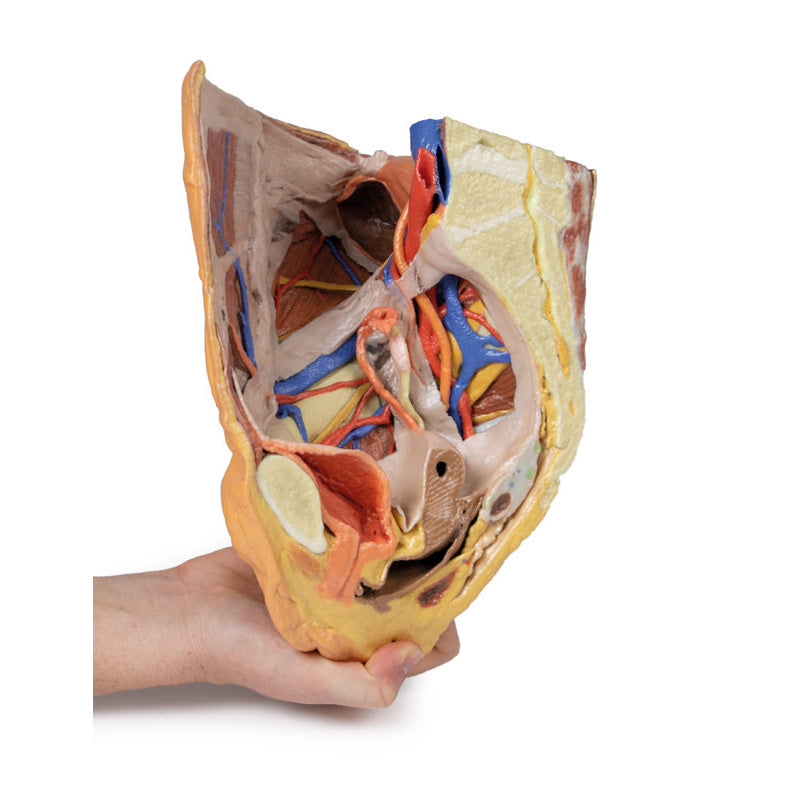

3D Printed Female right pelvis superficial and deep structures

The specimen has been sectioned transversely through the L4 vertebra, displaying a cross section of the colon, the epaxial musculature (psoas and quadratus lumborum muscles), and the abdominal wall musculature. The common iliac artery has been preserved from the level of the L4 vertebra, and its bifurcation into the external and internal iliac arteries can be observed at the level of the sacral promontory. Deep to the arteries the common iliac vein and the origin of the inferior vena cava are visible.

The external iliac artery and vein passes anteroinferiorly along the pelvic brim, giving rise to the inferior epigastric and deep circumflex arteries and veins before passing deep to the inguinal ligament. The psoas major muscle lies lateral to the external iliac artery, with the femoral nerve evident on its lateral margin close to the inguinal ligament. The lateral cutaneous nerve of the thigh travels laterally on the superficial surface of the iliacus muscle to exit the ‘false’ pelvis close to the anterior superior iliac spine.

Following the course of the internal iliac artery deep to the undissected peritoneum, many of the major branches of its anterior and posterior divisions can be identified. The anterior division divides (deep to the peritoneum) into the superior vesical, obturator and obliterated umbilical artery. With a course parallel to the obturator artery, the obturator nerve can be seen running over obturator internus before entering the obturator canal together with the obturator vein (nerve, artery, vein in that order from superior to inferior).

Branches of the posterior division of the internal iliac artery, iliolumbar, and several lateral sacral arteries, can be seen arising from the posterior aspect of the internal iliac just below the sacral promontory. Its terminal branch, the superior gluteal, usually passes posteriorly between the lumbosacral trunk and S1 nerve, but this is hidden from view. The internal iliac vein and its tributaries - the obturator veins, uterine vein, vesical veins, etc. can be seen lying internal to the nerves and muscles. The large S1 and S2 roots and the smaller S3 nerve root can be seen emerging from the sacral foramina to pass laterally where it is joined by the lumbosacral trunk (L4 and l5 roots) which is not visible, to form the sciatic nerve which exits through the greater sciatic foramen to emerge on the posterior aspect in the gluteal region. In the pelvis as these roots pass laterally they are interdigitated between the fibres of piriformis muscle.

The right ureter can be clearly seen as it passes inferiorly on the posterior abdominal wall superficial to psoas muscle. It passes over the pelvic brim at the bifurcation of the common iliac artery to descend on the lateral wall of the pelvis before passing medially in the base of the broad ligament (hidden from view as the peritoneal folds that ‘drape’ over the uterine [Fallopian] tubes are still intact) to reach the lateral angles of the bladder. In the pelvis the viscera which lies most anteriorly is the bladder. Its thick wall and cavity is easily seen in this mid-sagittal cut. Indeed the ureteric orifice can be seen at the angle of the trigone of the bladder on its internal mucosal surface. The relations of the uterus to the vagina are clearly visible in the mid-sagittal section. Indeed the anterior and posterior fornices are clearly seen as is the os of the cervix. The round ligament of the uterus has been removed along with some peritoneum to display the structures in the lateral pelvic wall. The entire right Fallopian tube is identifiable as it passes from the lateral aspect of the body of the uterus to terminate as the fimbria which overhangs the right ovary which is still held in place by its mesovarium. The ovary is attached laterally to the pelvic brim by the suspensory ligament of the ovary (sometimes called the infundibulopelvic ligament) which contains its named artery and veins. The ligament of the ovary is clearly visible leading from the medial aspect of the ovary to the lateral surface of the uterus.

There are only small cut surfaces of the rectum (visible as little islands of mucosa) visible on the sagittal cut surface suggesting that it is slightly off the midline plane. Some pararectal lymph nodes (coloured pale green) can be seen close to these islands of rectal mucosa. On the anterior aspect of the 3D print the inguinal ligament has been retained and deep to it the femoral artery, vein and nerve pass to the anterior compartment of the thigh.

In the gluteal region (note the femur has been removed to expose the acetabulum) the sciatic nerve can be seen emerging from the greater sciatic foramen (GSF) alongside the inferior gluteal vessels below the remains of the piriformis fibres, whereas the superior gluteal vessels and nerve emerges above the piriformis. Below these vessels the pudendal nerves and vessels can be seen exiting the GSF and passing over the sacrospinous ligament to enter the lesser sciatic foramen, thereby entering the perineum along the lateral wall of the ischioanal fossa.

3D Printed Female right pelvis superficial and deep structures

This 3D printed female right pelvis preserves both superficial and deep structures of the true and false pelves, as well as the inguinal ligament, the obturator membrane and canal, and both the greater and lesser sciatic foramina. Somewhat unique is the removal of portions of the peritoneum (a grayish colour) to create ‘windows’ displaying extraperitoneal structures.The specimen has been sectioned transversely through the L4 vertebra, displaying a cross section of the colon, the epaxial musculature (psoas and quadratus lumborum muscles), and the abdominal wall musculature. The common iliac artery has been preserved from the level of the L4 vertebra, and its bifurcation into the external and internal iliac arteries can be observed at the level of the sacral promontory. Deep to the arteries the common iliac vein and the origin of the inferior vena cava are visible.

The external iliac artery and vein passes anteroinferiorly along the pelvic brim, giving rise to the inferior epigastric and deep circumflex arteries and veins before passing deep to the inguinal ligament. The psoas major muscle lies lateral to the external iliac artery, with the femoral nerve evident on its lateral margin close to the inguinal ligament. The lateral cutaneous nerve of the thigh travels laterally on the superficial surface of the iliacus muscle to exit the ‘false’ pelvis close to the anterior superior iliac spine.

Following the course of the internal iliac artery deep to the undissected peritoneum, many of the major branches of its anterior and posterior divisions can be identified. The anterior division divides (deep to the peritoneum) into the superior vesical, obturator and obliterated umbilical artery. With a course parallel to the obturator artery, the obturator nerve can be seen running over obturator internus before entering the obturator canal together with the obturator vein (nerve, artery, vein in that order from superior to inferior).

Branches of the posterior division of the internal iliac artery, iliolumbar, and several lateral sacral arteries, can be seen arising from the posterior aspect of the internal iliac just below the sacral promontory. Its terminal branch, the superior gluteal, usually passes posteriorly between the lumbosacral trunk and S1 nerve, but this is hidden from view. The internal iliac vein and its tributaries - the obturator veins, uterine vein, vesical veins, etc. can be seen lying internal to the nerves and muscles. The large S1 and S2 roots and the smaller S3 nerve root can be seen emerging from the sacral foramina to pass laterally where it is joined by the lumbosacral trunk (L4 and l5 roots) which is not visible, to form the sciatic nerve which exits through the greater sciatic foramen to emerge on the posterior aspect in the gluteal region. In the pelvis as these roots pass laterally they are interdigitated between the fibres of piriformis muscle.

The right ureter can be clearly seen as it passes inferiorly on the posterior abdominal wall superficial to psoas muscle. It passes over the pelvic brim at the bifurcation of the common iliac artery to descend on the lateral wall of the pelvis before passing medially in the base of the broad ligament (hidden from view as the peritoneal folds that ‘drape’ over the uterine [Fallopian] tubes are still intact) to reach the lateral angles of the bladder. In the pelvis the viscera which lies most anteriorly is the bladder. Its thick wall and cavity is easily seen in this mid-sagittal cut. Indeed the ureteric orifice can be seen at the angle of the trigone of the bladder on its internal mucosal surface. The relations of the uterus to the vagina are clearly visible in the mid-sagittal section. Indeed the anterior and posterior fornices are clearly seen as is the os of the cervix. The round ligament of the uterus has been removed along with some peritoneum to display the structures in the lateral pelvic wall. The entire right Fallopian tube is identifiable as it passes from the lateral aspect of the body of the uterus to terminate as the fimbria which overhangs the right ovary which is still held in place by its mesovarium. The ovary is attached laterally to the pelvic brim by the suspensory ligament of the ovary (sometimes called the infundibulopelvic ligament) which contains its named artery and veins. The ligament of the ovary is clearly visible leading from the medial aspect of the ovary to the lateral surface of the uterus.

There are only small cut surfaces of the rectum (visible as little islands of mucosa) visible on the sagittal cut surface suggesting that it is slightly off the midline plane. Some pararectal lymph nodes (coloured pale green) can be seen close to these islands of rectal mucosa. On the anterior aspect of the 3D print the inguinal ligament has been retained and deep to it the femoral artery, vein and nerve pass to the anterior compartment of the thigh.

In the gluteal region (note the femur has been removed to expose the acetabulum) the sciatic nerve can be seen emerging from the greater sciatic foramen (GSF) alongside the inferior gluteal vessels below the remains of the piriformis fibres, whereas the superior gluteal vessels and nerve emerges above the piriformis. Below these vessels the pudendal nerves and vessels can be seen exiting the GSF and passing over the sacrospinous ligament to enter the lesser sciatic foramen, thereby entering the perineum along the lateral wall of the ischioanal fossa.